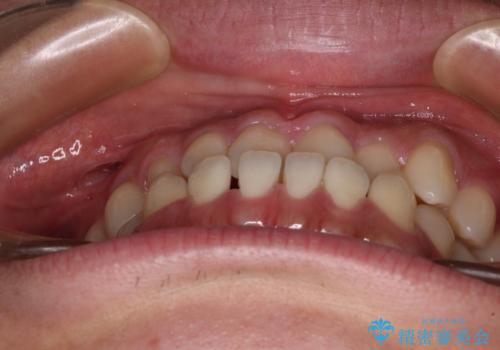

- 前歯のクロスバイトを気にして来院された患者様です。

1年半後に結婚式が控えているとのことで、ワイヤー矯正で早めに治療を終えることを希望されました。

骨格的に下顎が前方に位置していましたが、歯列矯正で改善できると判断し、ワイヤー装置にて矯正治療を行うこととしました。

骨格的な左右差も顕著であったため、正中は合わず、上下前歯の一部が接触しない咬み合わせとなることが予想されましたが、正中はもともとのズレが小さかったことから、合わせることができました。